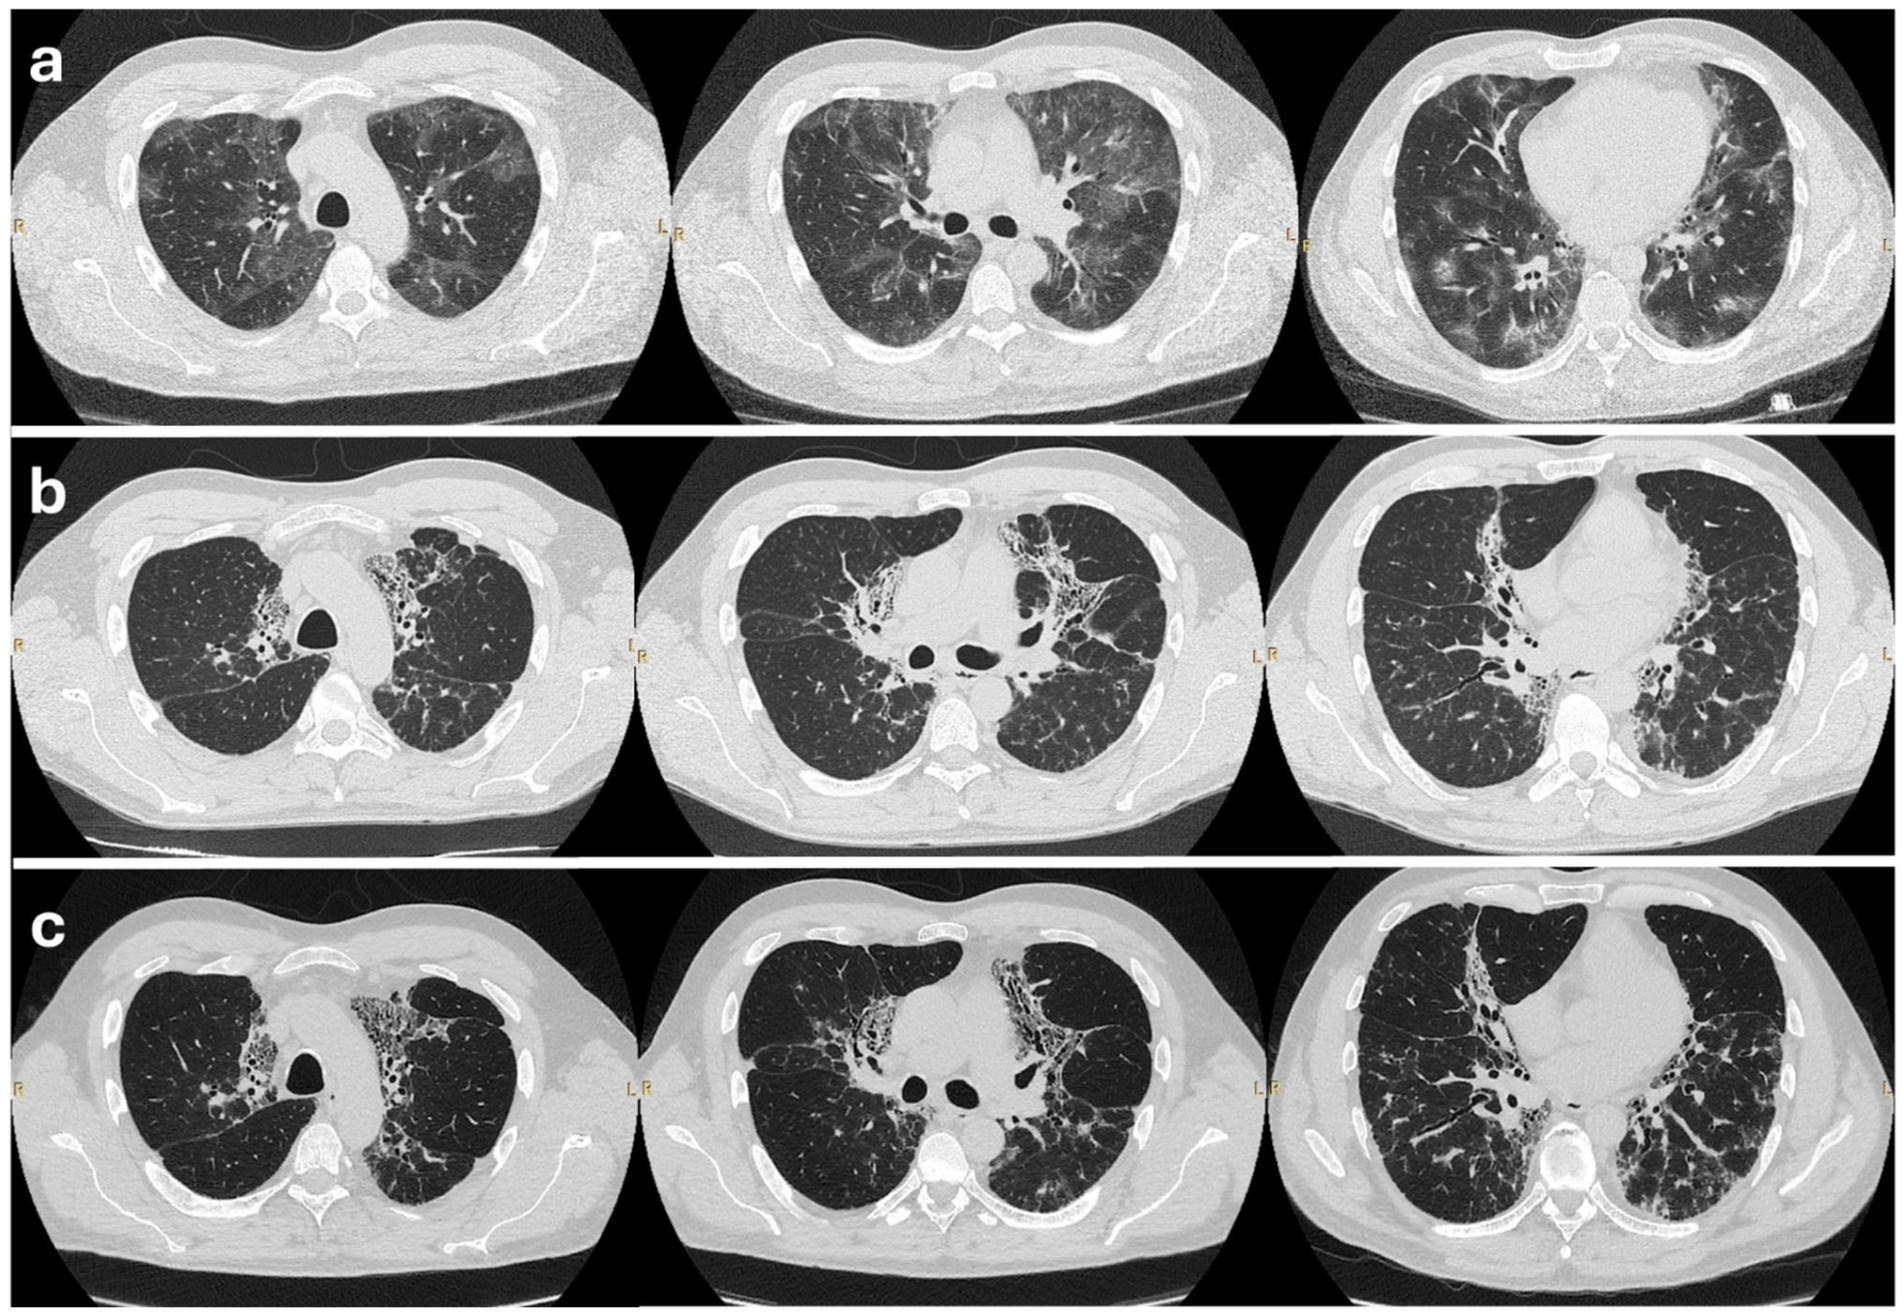

A 43-year-old Caucasian man presented to another center in 2019 with a 3-month history of a cough, a low-grade fever (up to 38 °C), and exertional dyspnea. He was a former smoker (approximately 7 pack-years, he quit in his 20s) and worked as a graphic designer with no known occupational/environmental exposures. His past medical history was unremarkable. Blood tests at presentation showed mild circulating eosinophilia (640 cells/uL) and a total IgE of 77 KUA/L; RAST testing revealed a non-clinically relevant mild sensitization to dust mites (d1 0.20 KUA/L, d2 0.19 KUA/L), and autoimmune screening (ANA, ENA, ANCA, rheumatoid factor, anti-citrullinated protein antibodies, myositis-specific autoantibodies, and myositis-associated autoantibodies) was negative. A high-resolution CT (HRCT) demonstrated multiple bilateral patchy opacities, including ground-glass infiltrates with some pseudonodular consolidations and bronchial dilatation, more prominent in the peripheral regions (Figure 1a). Bronchoscopy with bronchoalveolar lavage (BAL) showed a BAL fluid with an eosinophil differential count of 40%. A transbronchial lung biopsy revealed prominent eosinophilic infiltration without evidence of vasculitis or granulomatous inflammation. Pulmonary function tests (PFTs) showed normal baseline spirometry, with a reduced diffusing capacity of the lung for carbon monoxide (DLCO, 61%). A non-specific bronchial challenge with methacholine excluded the diagnosis of bronchial asthma. Additionally, there were no sino-nasal symptoms (including nasal congestion, rhinorrhea, hyposmia, facial pain, or history of chronic sinusitis) or clinical features suggestive of the eosinophil-associated involvement of other organs. Based on these findings, along with the exclusion of secondary causes of eosinophilia, a diagnosis of idiopathic chronic eosinophilic pneumonia was made.

Figure 1.

High-resolution CT chest scans of the patient at three stages. (a) The inflammatory phase (2019): Baseline HRCT showing bilateral patchy ground-glass opacities and consolidations. These changes predominantly involve subpleural regions, consistent with active CEP. (b) The fibrosing phase (2021–2023): HRCT after years of relapsing disease off steroids, demonstrating an evolution towards fibrosis. Reticular opacities and traction bronchiectasis in the upper lobes can be seen. (c) Post-treatment (2025): HRCT after 8 months of mepolizumab therapy, showing stable fibrotic changes. Reticulation and bronchiectasis persist unchanged; no new inflammatory lesions are seen.

The patient was started on high-dose oral prednisone (50 mg daily) from May 2019. His respiratory symptoms and radiographic opacities improved significantly within weeks. After 2 months, the prednisone was gradually tapered. However, the patient developed adverse effects consistent with glucocorticoids toxicity, including multiple osteoporotic fractures and avascular necrosis of the left femoral head, ultimately requiring total hip arthroplasty in 2020. Bone densitometry revealed osteoporosis of the lumbar spine and osteopenia of the right femur. Due to these complications, glucocorticoids were discontinued by mid-2020. Over the subsequent year of therapy, the patient’s respiratory condition slowly worsened. By late 2020 and early 2021, he reported recurrent dry cough and exertional dyspnea, and prednisone was reintroduced (starting from 25 mg per day) between the end of 2020 and March 2021. A HRCT performed in July 2021 revealed a progression towards fibrosis with an interstitial thickening within areas of parenchymal band-like opacities associated with traction bronchiectasis, along with residual patchy ground-glass opacities and consolidations (Figure 1b). These findings were consistent with an evolution to fibrotic CEP. PFTs at that time showed a mild restrictive defect [total lung capacity (TLC) 4.99 L, 79% predicted] with a reduced DLCO of 56% predicted (Figure 2). Another course of prednisone was started at a dose of 15 mg daily, with concomitant treatment for bone protection, including a bisphosphonate and calcium and vitamin D supplementation.

After 8 months of continuous mepolizumab therapy, at the February 2025 visit, the patient’s condition was stable and improved relative to the pre-biologic baseline. FEV1 had risen to 2.54 L (71% pred.), and FVC was 3.22 L (73% pred.), with TLC 3.90 L (57% pred.). DLCO was 46% pred. (Figure 2). Meanwhile, he had not experienced any CEP relapses or acute worsening. Follow-up imaging demonstrated stability of the fibrosing changes: the HRCT performed in January 2025 showed an unchanged extent of reticular fibrosis and traction bronchiectasis compared to mid-2024, with no new consolidations or ground-glass opacities (Figure 1c). Radiological exams were reviewed by independent radiologist and also by an expert thoracic radiologist in the multidisciplinary team. Owing to the clinical and radiologic stabilization, mepolizumab was continued. Introduction of antifibrotic therapy (such as nintedanib) was considered but ultimately deferred, since the criteria for progressive fibrosing interstitial lung disease (ILD) were not met (the patient had stable lung function and no radiologic progression while on mepolizumab). The patient continues mepolizumab with regular follow-up visits.

A key novelty of this case lies in the presence of established pulmonary fibrosis. In “pure” CEP (without fibrosis), successful biologic therapy often yields the rapid radiographic clearing of eosinophilic pneumonia lesions [6]. In our patient, fibrotic CEP is characterized by an irreversible architectural distortion—reticulation and traction bronchiectasis—that persists despite treatment [8]. In our patient, even after mepolizumab, the HRCT showed residual reticular changes and traction bronchiectasis consistent with fibrosis. These fibrotic changes had accumulated during the years of inadequately controlled inflammation. The goal of therapy in fibrotic CEP is primarily to halt further eosinophil-driven damage, rather than the regression of fibrosis. Mepolizumab appeared to achieve this goal: the fibrotic pattern remained stable on serial imaging, with no extension or new fibrotic lesions. The lung function (FEV1, FVC, DLCO) actually improved slightly with the therapy, likely reflecting the resolution of active inflammation and possibly some recovery of reversible components (e.g., ventilation in areas of the lung that were inflamed but not yet fibrotic).